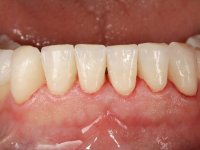

Paciente do sexo masculino, com 36 anos, não fumador. Fez tratamento ortodôntico e reabilitou esteticamente o sector anterior com restaurações em resina composta. As restaurações apresentavam um aumento vertical médio de 2 mm em relação o bordo incisal. Apresentavam-se esteticamente satisfatórias, mas com algumas fraturas incisais. O dente 1.5 apresentava um processo apical e o dente 2.6 apresentava tratamento endodôntico e uma lesão endo-periodontal. No maxilar inferior no local do dente 3.5 apresentava um implante com uma coroa aparafusada e o dente 8.5 ainda estava presente em boca com agenesia do dente 4.5. O paciente apresentava uma ligeira perda da dimensão vertical da oclusão provavelmente associada a um visível desgaste das superfícies oclusais. O periodonto era espesso e apresentava uma excelente higiene oral.

Após análise clínica e imagiológica foi proposto ao paciente recuperar a dimensão vertical da oclusão essencialmente à custa de incrementos oclusais inferiores utilizando “overlays” no sector posterior e facetas no sector anterior. A coroa aparafusada sobre o implante 3.5 seria substituída, no sentido de acompanhar este incremento. Na maxila o dente 2.6 teria extração indicada e posteriormente seria reabilitado com um implante e respetiva coroa. No sentido de reabilitar esteticamente o paciente duma forma minimamente invasiva, foi proposta a colocação de facetas feldespáticas no sector antero-superior. O objetivo de aumentar ligeiramente a D.V.O., teria como função “proteger” eficazmente o sector antero-superior.

Realizado o diagnóstico e tomada a decisão quanto ao tratamento a executar, tornou-se importante definir qual a sequência de trabalho a adotar no sentido de conseguir a reabilitação da D.V.O. (V.D.O), de forma progressiva e equilibrada. Na primeira fase fez-se uma pré-impressão da arcada inferior com silicone tipo “putty” e em seguida realizou-se o preparo dentário de todo o sector posterior. O preparo para os overlays foi feito coronalmente à linha amelo cementaria no sentido de ser o mais conservador possível. A impressão foi feita com técnica de dupla mistura após afastamento gengival realizado com pasta de caulino. A provisória foi realizada com resina composta de polimerização dual. Em laboratório foram realizados os overlays após se ter aberto ligeiramente (1,5mm) a D.V.O. nos modelos montados em articulador semi-ajustável. Simultaneamente o sector antero-inferior foi encerado no sentido de acompanhar este aumento da D.V.O. Também foi confecionada uma chave de silicone translucido para posterior confeção dos provisórios antero-inferiores. Em boca foi primeiro realizada a provisionalização dos dentes anteriores utilizando resina composta previamente aquecida após preparação das superfícies dentárias para a adesão. Foi colocado o dique de borracha para promover o isolamento absoluto e posteriormente foram colados os overlays. Em laboratório foi realizada nova chave de silicone para confecionar os provisórios antero-superiores. Seguidamente em boca foram preparados os seis dentes antero-superiores após colocação do fio de afastamento gengival. Feita a preparação adequada das superfícies dentárias foi realizada a impressão com técnica de dupla mistura e a respetiva provisória. Em laboratório foram confecionadas 6 facetas feldespáticas num modelo de trabalho tipo “Geller”. A provisória foi removida e as facetas foram coladas em boca utilizando um isolamento relativo competente. Esta opção foi tomada em virtude de uma prévia experiencia negativa com a colocação do dique de borracha na mandibula. Após a colagem dos laminados antero-superiores foram dadas 12 semanas para avaliar a adaptação do paciente à nova situação e então iniciar a confeção das facetas antero-inferiores. Após colocação do fio de afastamento gengival. foram feitos os preparos dentários adequados e em seguida foi feita a impressão. Também foi feita a preparação do dente 3.4 que, entretanto, tinha sofrido uma fratura do overlay. As facetas e a restauração do 3.4 foram realizadas num modelo de trabalho tipo “Geller”. Após remoção da provisória, as facetas foram coladas em boca, utilizando um isolamento relativo pelas razões apontadas anteriormente. Após colocação do trabalho o paciente foi reabilitado por outros colegas com um implante na zona do 2.6 e substituição da coroa aparafusada sobre o implante colocado no local do 3.5. Posteriormente surgiram fraturas nos overlays dos dentes 4.7 e 3.7 que foram reabilitados com overlays em Zr.